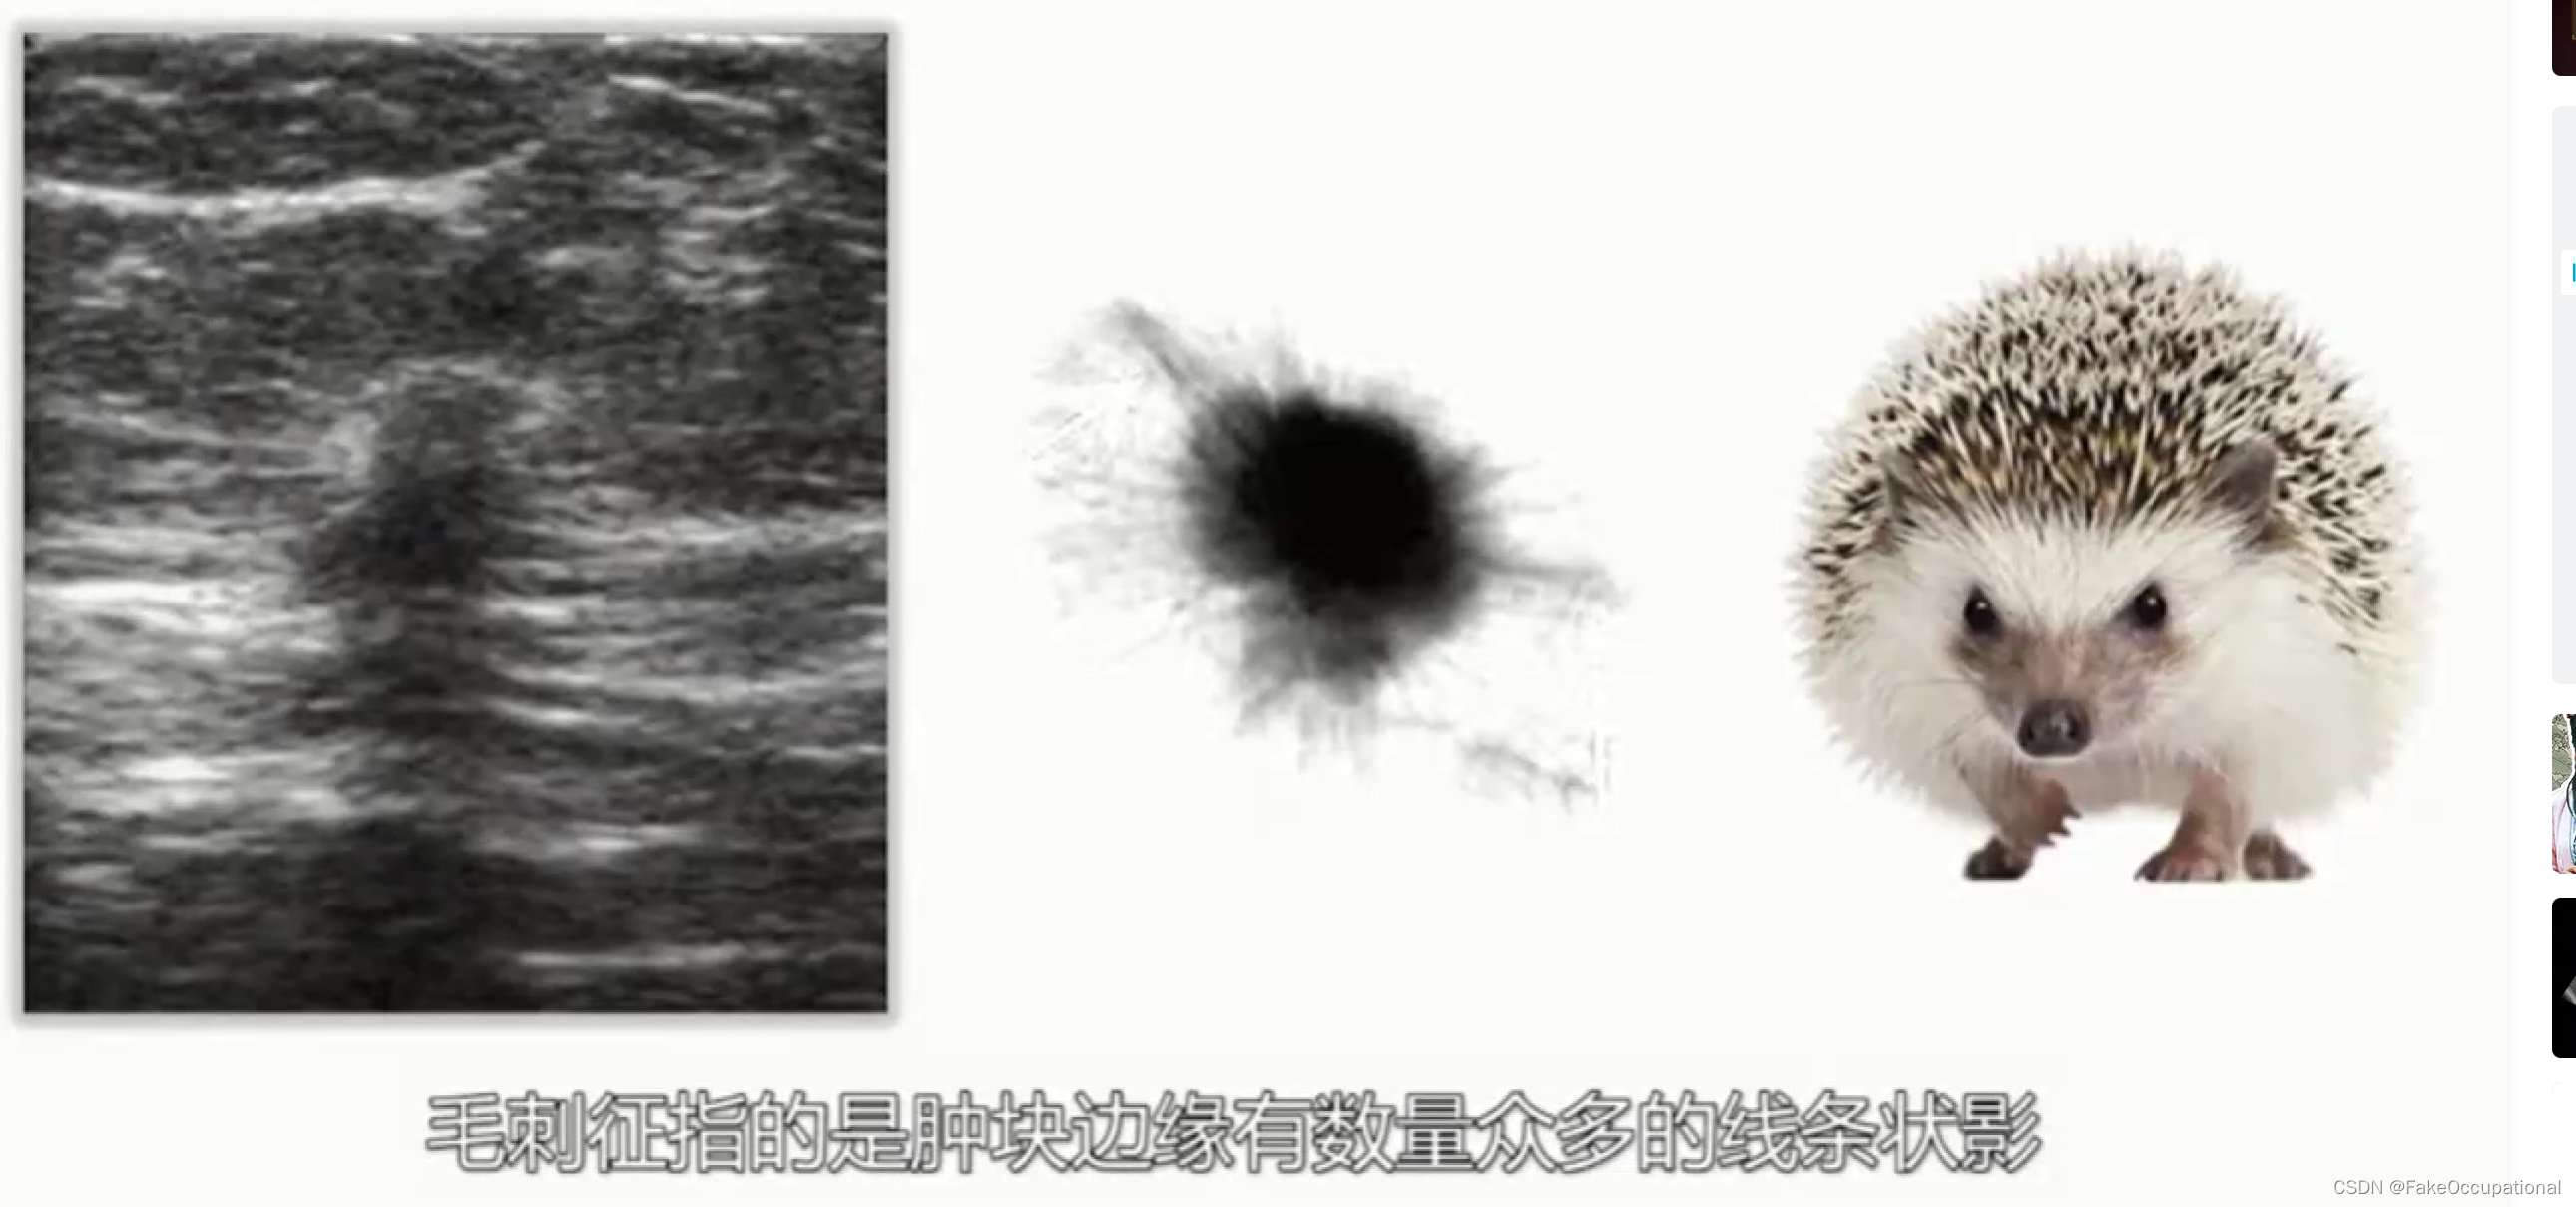

乳腺癌